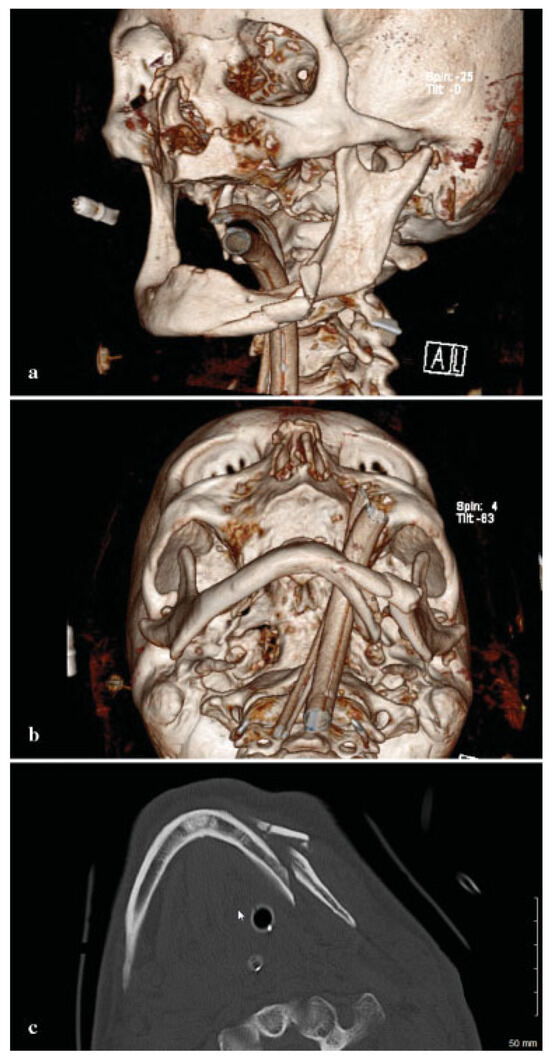

Owing to the significant injury to the anterior and posterior column of the cervical spine, a fusion was performed of C5–T1. Prior to surgery, he was kept in a cervical spine collar. To minimize the time in the operating room (OR) and manipulation of the displaced, atrophic mandible, his initial CT scans were used to fabricate a model to facilitate the correction of the complex mandible fracture. Turnaround time was 5 days. Using three-dimensional (3D) software for VSP (Materialize, Plymouth, MI), the midline of the larger segment of the mandible was aligned with the midline of the maxilla (Figure 2a,b). A mirror image was created using the opposing uninjured mandibular body (Figure 3a,b). A stereo-lithographic model was fabricated facilitating the preoperative bending of a 2.5-mm reconstruction plate, based on the virtually planned model (Figure 4). The plate was contoured to the model the evening before surgery.

Figure 2. (a) Preoperative submental image prior to manipulation. (b) Midline of mandible aligned with midline of the maxilla.